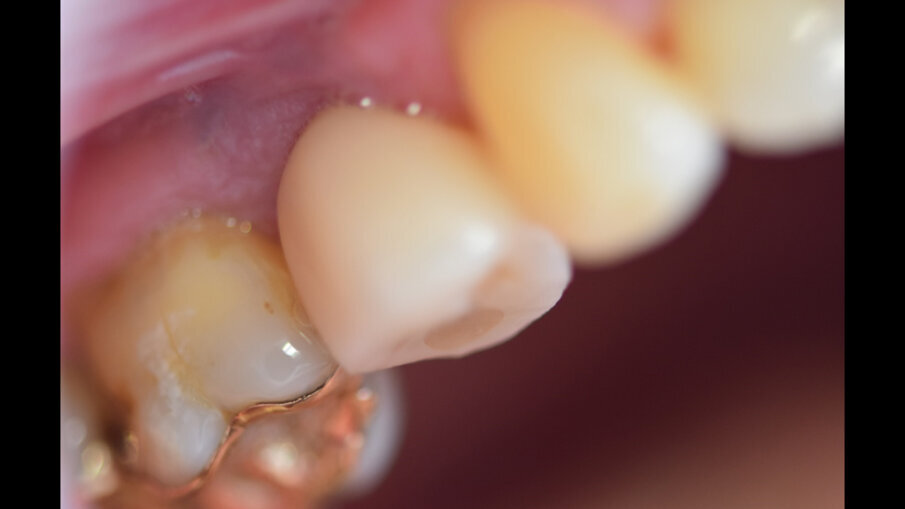

Uvádí se, že kouření obecně zvyšuje riziko selhání implantátů a výskytu periimplantitidy. Jedním z možných mechanismů, které mohou vést ke zvýšené míře selhání implantátů, je snížený průtok krve a přímé nepříznivé účinky na osteoblasty. Mají-li se zavádět implantáty u kuřáků, je nutná dobrá kvalita kosti. V naší studii byly nezbytné procedury augmentace kosti u 62 případů.

Kouření tabáku snižuje aktivitu leukocytů. Má vliv na krevní cévy a snižuje schopnost hojení organismu a oseointegrace dentálních implantátů. Kouření má přímý vliv na funkci osteoblastů.2 Přesný mechanismus, jakým kouření snižuje schopnost hojení ran, je dosud neznámý. Kouření zvyšuje riziko průniku bakterií, které mohou způsobit periimplantitidu. Předpokládá se, že nikotin a chemické látky obsažené v tabákovém kouři vyvolávají v tkáních (gingiva a alveolární kost) kolem implantátů oxidační stres.3, 4 Z důvodu podpory oseointegrace by proto bylo vhodné přestat kouřit alespoň po dobu osmi týdnů po implantaci.

Ze 721 implantátů selhalo celkem 65 implantátů. Míra úspěšnosti tedy ve výsledku byla 90,98 %, tedy nižší než v naší předchozí studii provedené u nekuřáků, u nichž byla míra úspěšnosti 98,70 %.2 U skupiny neúspěšných implantátů selhala většina z nich (74,5 %) dva až čtyři týdny po zavedení v důsledku nedostatečné oseointegrace. Periimplantitida se vyskytovala u 20 % neúspěšných implantátů. To lze přičíst špatné ústní hygieně a tvorbě plaku. U 4,6 % případů se periimplantitida objevila v rozmezí jednoho až tří let po zavedení implantátu v důsledku mechanických problémů po úbytku kosti. Nebyla zjištěna žádná souvislost mezi délkou a průměrem implantátu a mírou selhání, ani mezi počtem vykouřených cigaret a mírou selhání implantátu.